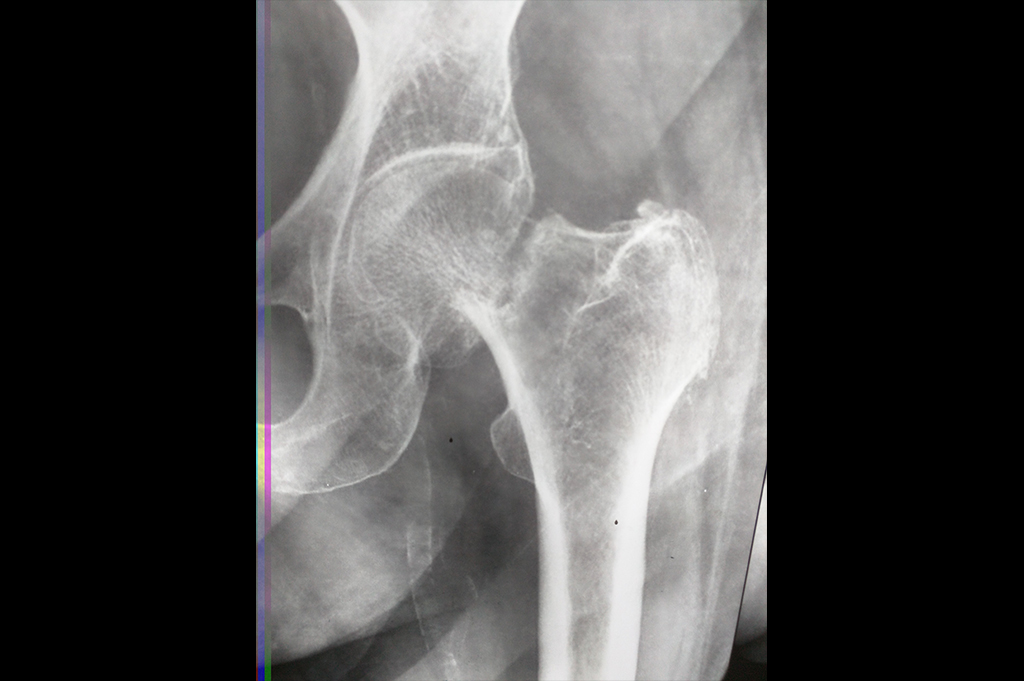

Neck Femur Fracture